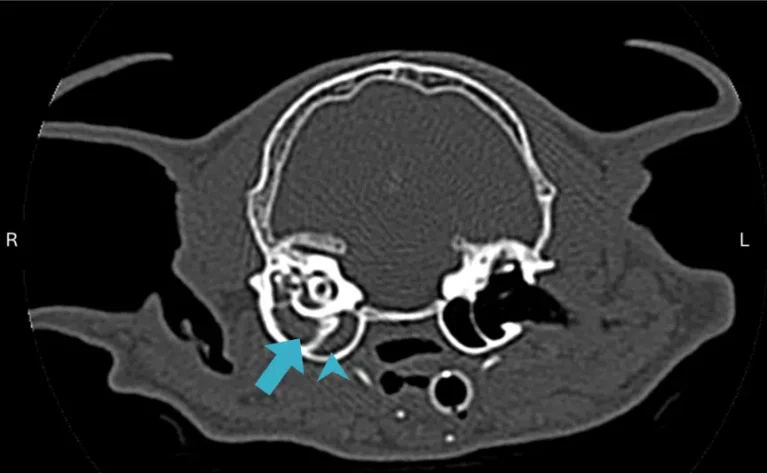

Bản chất: Là sự lan rộng của nhiễm trùng từ tai ngoài xuyên qua màng nhĩ (tai giữa) vào đến ốc tai và hệ tiền đình (tai trong).

Màng nhĩ đóng vai trò là lá chắn cơ học tối quan trọng được mô tả trong cấu tạo giải phẫu tai chó mèo. Khi tình trạng viêm tai ngoài ở chó mèo kéo dài không được điều trị, áp lực dịch mủ tích tụ ở đáy ống ngang sẽ tạo ra một lực ép khủng khiếp lên màng nhĩ.

Khi vi khuẩn vượt qua tai giữa để tiến vào tai trong (Otitis Interna), chúng sẽ xâm chiếm ốc tai và cơ quan tiền đình – nơi điều khiển khả năng thăng bằng. Đây là lúc thú cưng xuất hiện “Hội chứng tiền đình” với các biểu hiện đặc trưng: chó bị nghiêng đầu về phía tai viêm, mèo mất thăng bằng và có xu hướng ngã đổ về một bên.

Sự rung giật nhãn cầu (mắt chuyển động nhanh liên tục) là bằng chứng cho thấy não bộ đang bị nhiễu loạn tín hiệu định vị. Nếu không can thiệp kịp thời, biến chứng viêm tai thần kinh có thể dẫn đến liệt mặt hoặc viêm màng não.